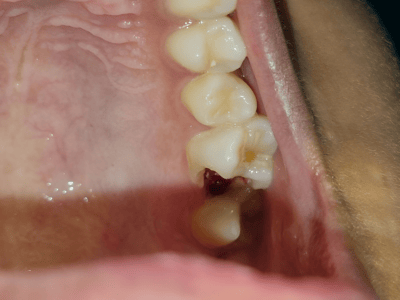

provides expert treatment for gum diseases, receding gums, and dental implant procedures using the

high standards of hygiene and comfort. Her expertise includes laser dentistry, cosmetic smile

From routine checkups to complex gum treatments, dental implants, laser dentistry, root canal treatments (RCT), and smile

Dr. Bhardwaj specializes in Periodontics, offering treatments for gum diseases, dental implants, laser dentistry, root canal treatments (RCT), teeth whitening, smile makeovers, and general dental care.